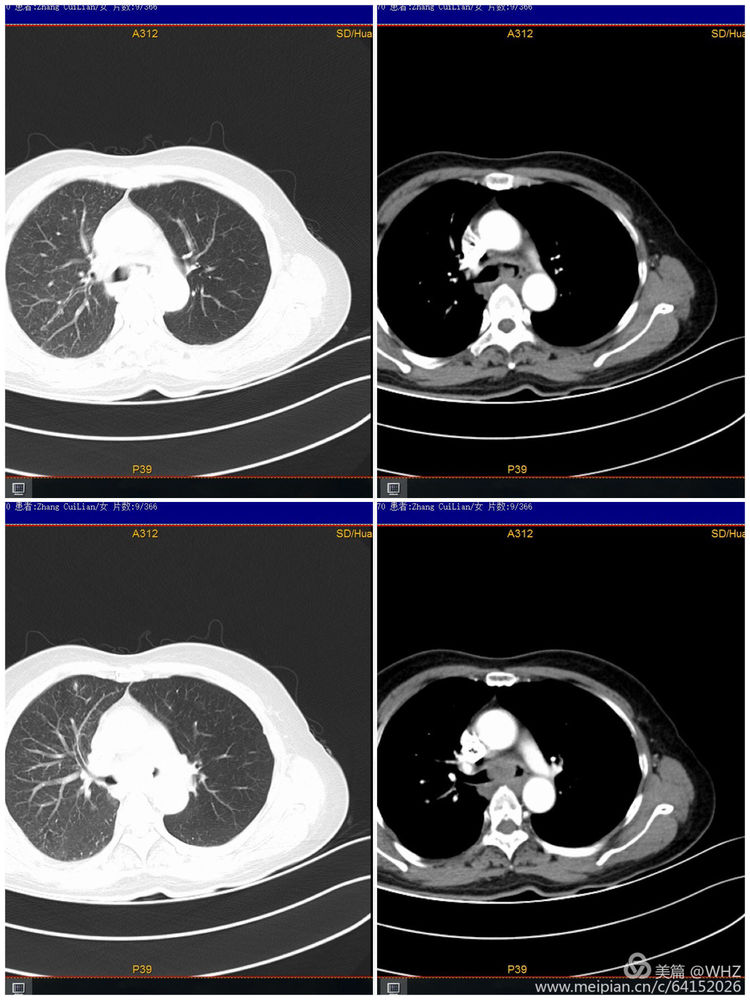

63岁的张女士,因咳嗽、喘憋了1个多月来院检查,查体显示双肺呼吸音粗,闻及吸气相哮鸣音。通过CT等检查诊断为肺部肿瘤,支气管镜检查发现左主支气管狭窄,如不及时处理随时会发生呼吸道梗阻而危及生命。

胸部CT示经气管镜活检病理为低分化腺癌伴灶性鳞状分化,基因监测无突变。

治疗前与治疗后比较